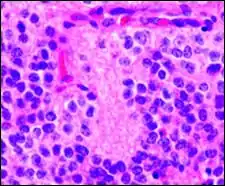

Pineocytomatous/neurocytic pseudorosettes

Histologic features of these two tumors are virtually identical, including their tendency to form neuropilrich rosettes, referred to as pineocytomatous/neurocytic rosettes in central neurocytoma. Both are quite similar to the Homer Wright rosette, but they are generally larger and more irregular in contour. The cells of the pineocytomatous/neurocytic rosettes are also considered to be much more differentiated than the cells forming Homer Wright rosettes in that the nuclei are slightly larger, more rounded, much less mitotically active, and paler or less hyperchromatic. In rare cases, these rosettes may aggregate in a sheet of back-to-back clusters resembling field stone pavement.[2]

Micrograph of pineocytomatous/neurocytic pseudorosettes

Structure of pineocytomatous/neurocytic pseudorosettes